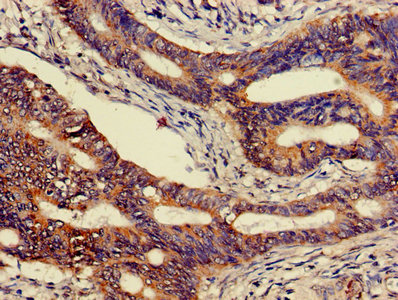

CEACAM7 Antibody (CSB-PA005167LA01HU)

Immunohistochemistry of paraffin-embedded human colon cancer using CSB-PA005167LA01HU at dilution of 1:100